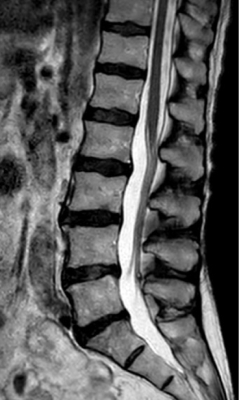

T2w TSE

Ingenia Ambition 1.5T